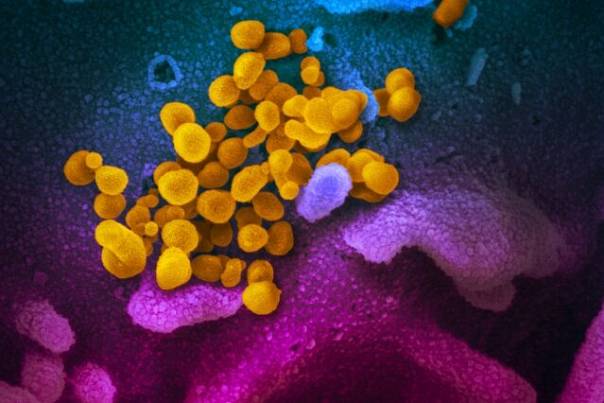

Троянский конь в молекулярных масштабах: ученые разрабатывают метод борьбы с коронавирусом посредством его же белка Исследователи из университета Вандербильта пристально рассматривают белок, ответственный за развитие и вирулентность нескольких видов коронавирусов, в том числе и SARS-CoV-2. С помощью изучаемого белка...